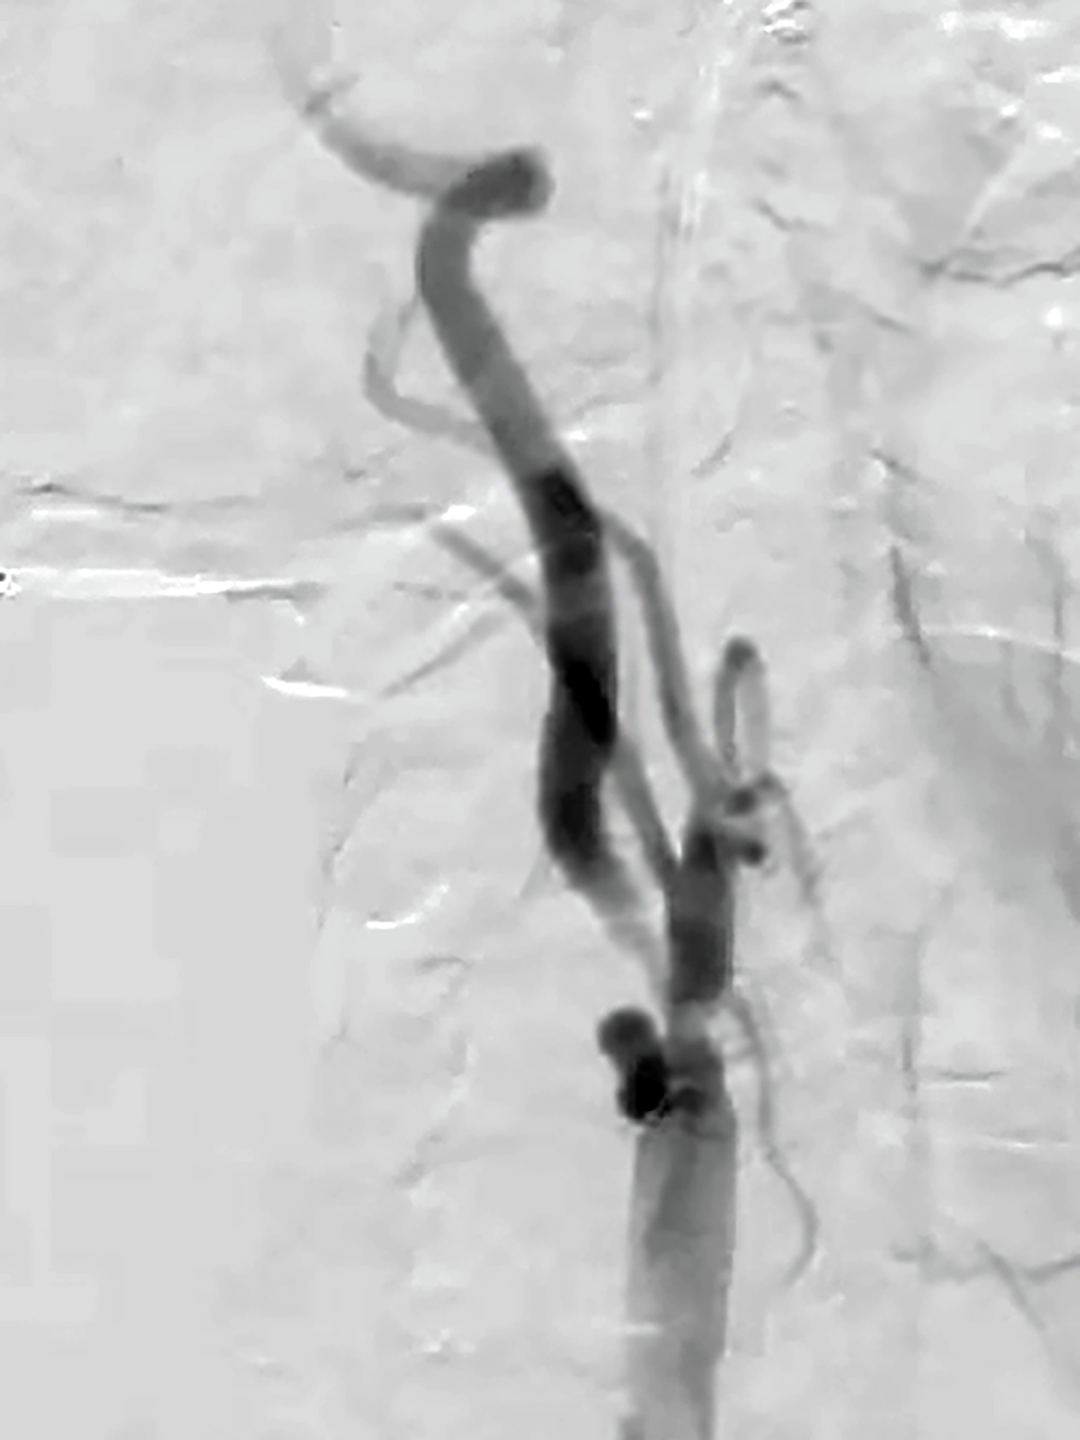

After demonstrating Mr. M’s capacity to tolerate high flow on the flow reversal system, a balloon was used to pre-dilate the lesion followed by placement of the carotid stent. A completion angiogram demonstrated good angiographic results (Figure 2), precluding the need for post-dilatation. The proximal common carotid clamp was then removed.

At Penn, CT images revealed a high-grade stenosis (74%) of the right carotid bulb and internal carotid artery (Figure 1), with evidence of softer plaque in the carotid bulb, and occlusion of the left carotid artery. These scans also found a very high bifurcation of the external and internal carotids, placing Mr. M in the high risk category for carotid endarterectomy.